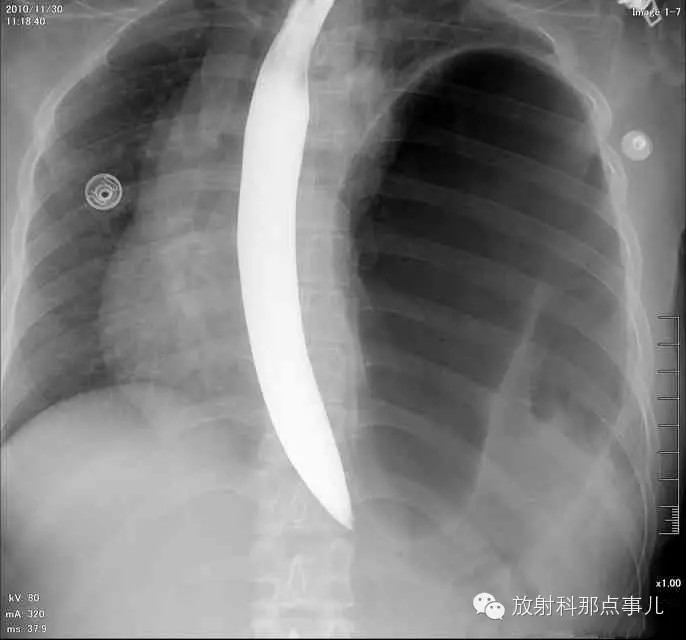

【病例学习】膈疝一例X线诊断

24岁,女性,腹痛渐加重并呕吐。

患者系顺产后18天产妇,产后感觉腹部疼痛不适,自认为正常反应,近两日因胸闷、腹部疼痛加剧伴呕吐来院就诊。

门诊腹部透视发现左侧胸腔巨大气液平面,为排除膈疝口服钡剂,但造影剂未见进入胃内。嘱住院,外科给予胃肠减压、补液等处理常规处理(未引流出明显气、液体)。5个半小时后再次检查,见少量造影剂进入消化道;为进一步了解情况,予泛影葡胺分别经胃管推注及口服,但均未进入胃内。当天进行外科急诊手术。

大部分胃、脾及横结肠均经过胸肋三角疝入左侧胸腔内,并见疝环形成。